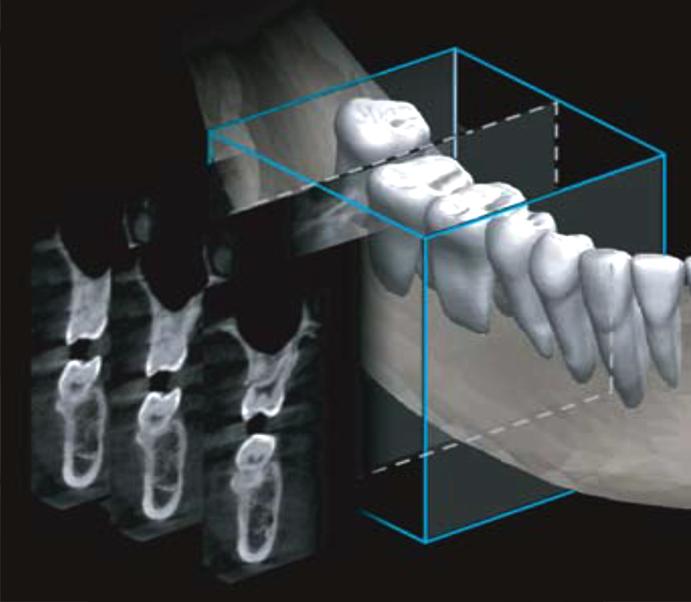

CUST (Cubical Semi Tomographic)

A CUST 256 keresztmetszeti felvétel felhasználásával készíti el az implantátum-diagnózishoz szükséges képeket. Gazdaságosabb megoldást kínál, mint a 3D CT.